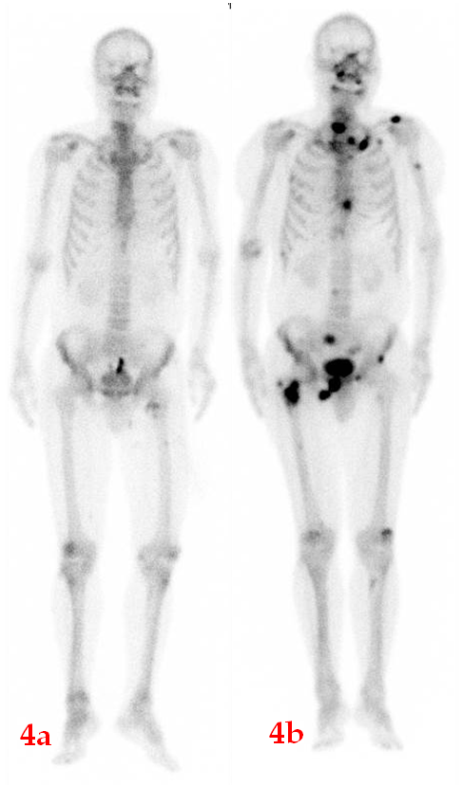

肺腺癌患者,2018年12月ECT檢查(4a圖)未見明顯異常;期間未復(fù)查;2023年5月骨痛來診,ECT檢查(4b圖)顯示全身多發(fā)骨轉(zhuǎn)移。